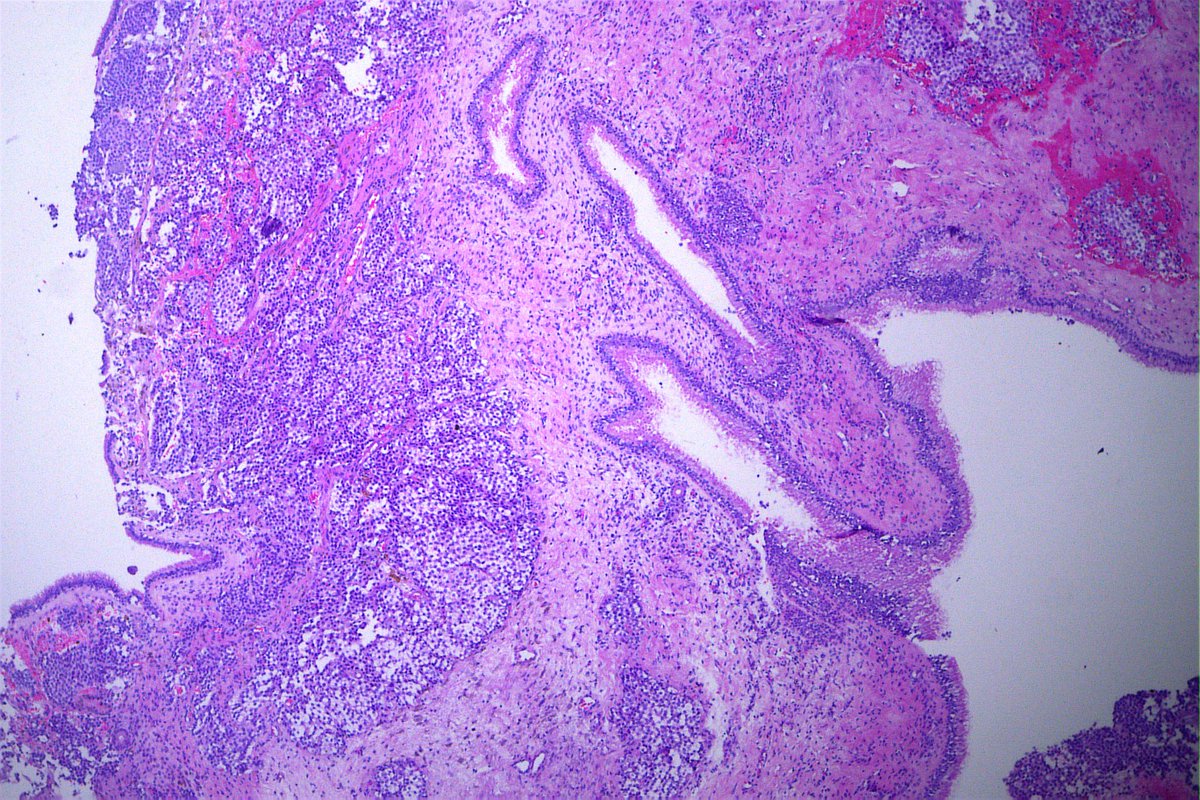

Case of the day. M, 30 years old, with weight loss, pulmonary consolidation area, mediastinal lymph node enlargement, and endobronchial polypoid lesions. Bronchial biopsy performed. #pulmpath #pathology